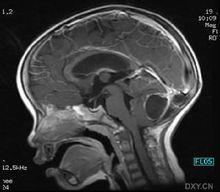

中樞神經系統苯乙酸睪酮在胚胎期和嬰兒期發展大腦某些區域,從而影響大腦的發育。在青春期,隨著性激素濃度的增加,這些大腦結構以及全部行為技能得以正式形成。

中樞神經系統